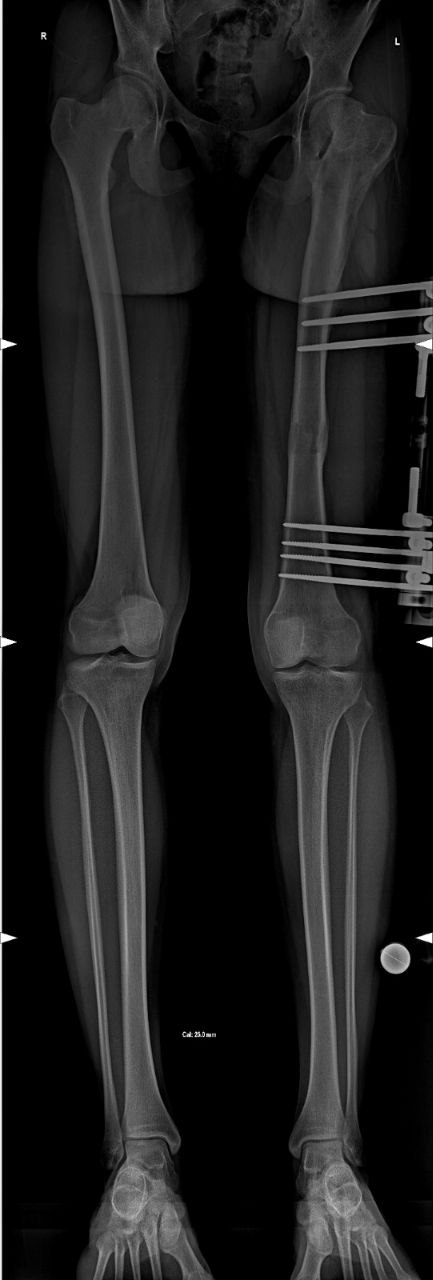

Пациентка, 12 лет. На фоне лечения патологии левого тазобедренного сустава сформировалось укорочение левого бедра до 3,5 см. Через 9 месяцев после оперативного лечения достигнута полная коррекция разновеликости.